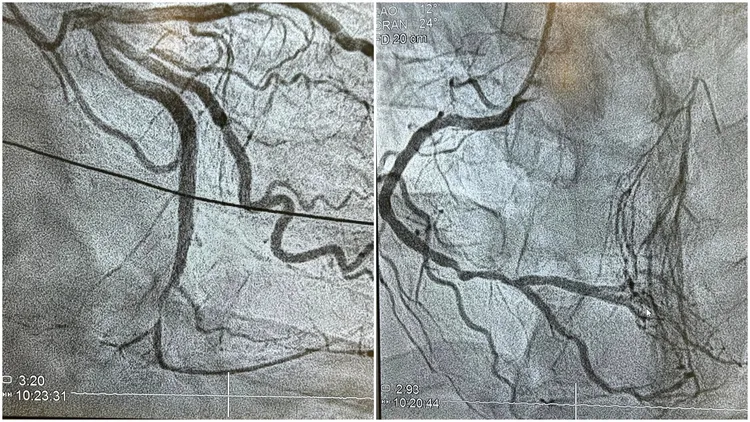

陳冠任醫師表示,患者輕忽膽固醇問題,心臟血管嚴重堵塞。翻攝臉書粉專「冠任醫師的異想世界」

新光醫院心臟內科主治醫師陳冠任日前在臉書粉專「冠任醫師的異想世界」訴說一個病例,一名41歲的壯年男子,在公司的健身房突發心因性猝死,無呼吸心跳,雖經急救幸運撿回一命恢復意識,但是發現心臟血管嚴重堵塞,最好的一條堵塞了80%、次好的塞了90% ,最重要的一條幹道則完全阻塞(100%阻塞)。患者清醒後訝異地說,自己不菸不酒、無不良嗜好、無高血壓糖尿病,還定期運動,血管怎會栓塞得如此嚴重?

陳冠任解釋,從患者去年底的健檢報告可發現,好膽固醇(高密度脂蛋白)HDL過低,壞膽固醇(低密度脂蛋白)LDL又異常高,兩者差距甚遠,導致血管經年累月慢慢退化狹窄,終至三條血路都坑坑疤疤藕斷絲連,最後才發生這樣的憾事。